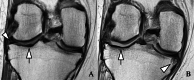

Methods: Participants with baseline opioid use (n=181) and who continued use for ≥1 year between baseline and 4-year follow-up (n=79) were included from the Osteoarthritis Initiative cohort and frequency matched with non-users (controls) (1:2). Whole-Organ Magnetic Resonance Imaging Scores (WORMS) were obtained, including a total summation score (WORMS total, range 0-96) and subscores for cartilage (0-36), menisci (0-24), and bone marrow abnormalities and subchondral cyst-like lesions (0-18, respectively). Knee Injury Osteoarthritis Outcomes score (KOOS) symptoms, quality of life (QOL), and pain were also obtained at baseline and follow-up (range 0-100; lower scores indicate worse outcomes). Using linear regression models, associations between baseline and longitudinal findings were investigated. As pain may modify observations, a sensitivity analysis was performed for longitudinal findings. All analyses were adjusted for sex, BMI, age, race, and Kellgren-Lawrence grade.

Results: Opioid users had greater structural degeneration at baseline (WORMS total: Coef. [95% CI], P; 7.1 [5.5, 8.8], <0.001) and a greater increase over 4 years (4.7 [2.9, 6.5], <0.001), compared to controls. Cartilage and meniscus scores increased greater in opioid users, compared to controls (P≤0.001), and findings withstood the adjustment for baseline pain (P≤0.002). All baseline KOOS scores were lower in opioid users compared to controls (P<0.001). QOL loss was greater, when adjusted for baseline KOOS pain (QOL -6.9 [-11.6, -2.1], 0.005).